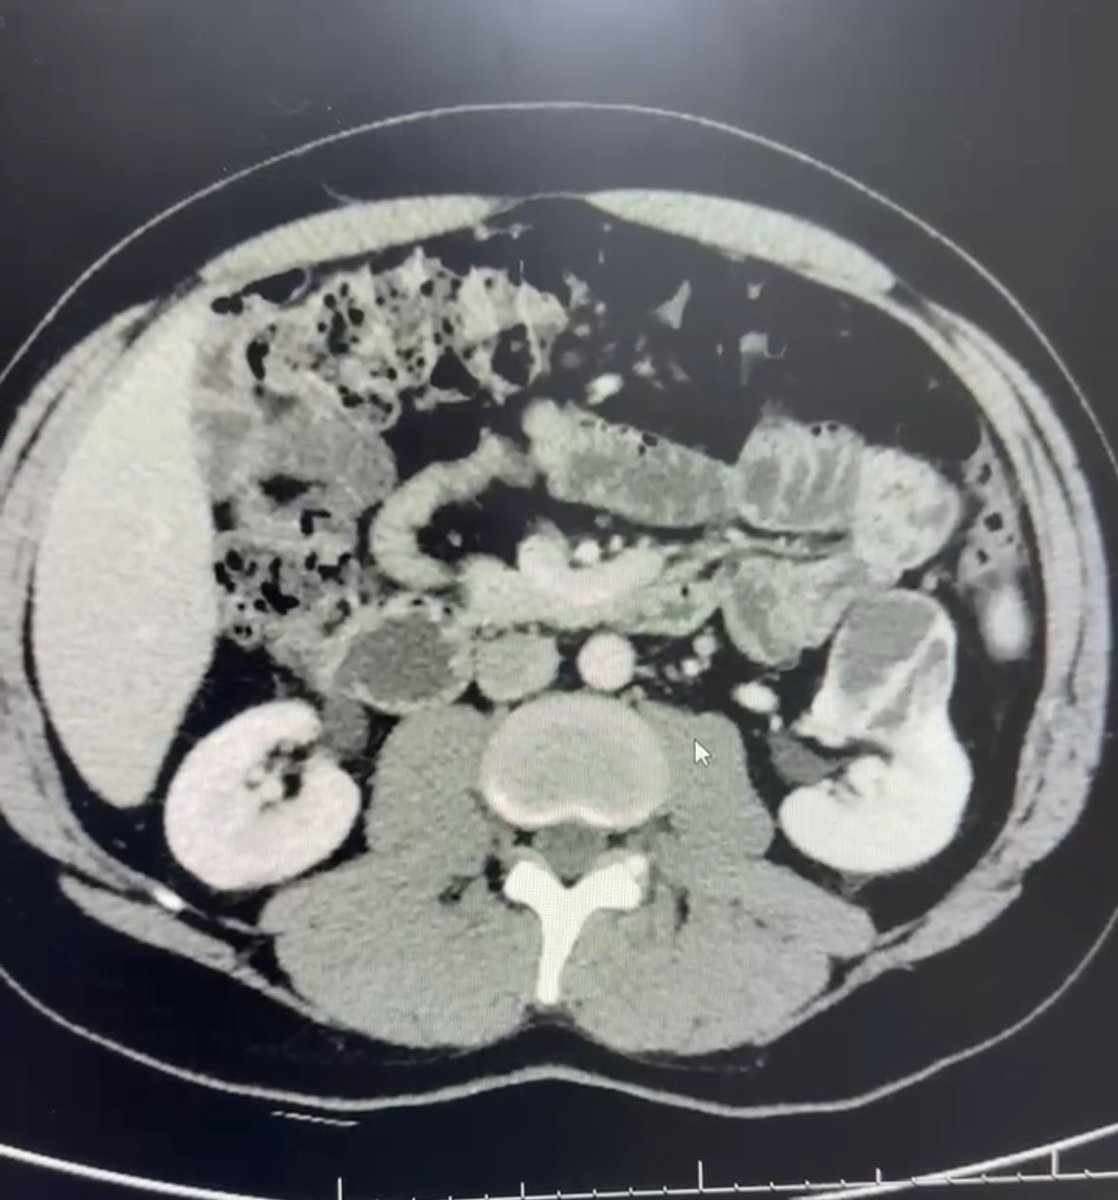

Laparoscopic Partial Nephrectomy for a 4 cm mid-pole Bosniak 4 cyst

Warm ischemia time: 21 minutes

Many thanks to @AlmaimanSS for the excellent assistance and @sbinhamrii for ensuring we have the best equipment—helping @SMCH_Riyadh maintain the highest surgical standards.

عملية استئصال جزئي للكلية باستخدام المناظير بدون الفتح الجراحي الكامل.

الغرض من العملية: وجود ورم بالكلية